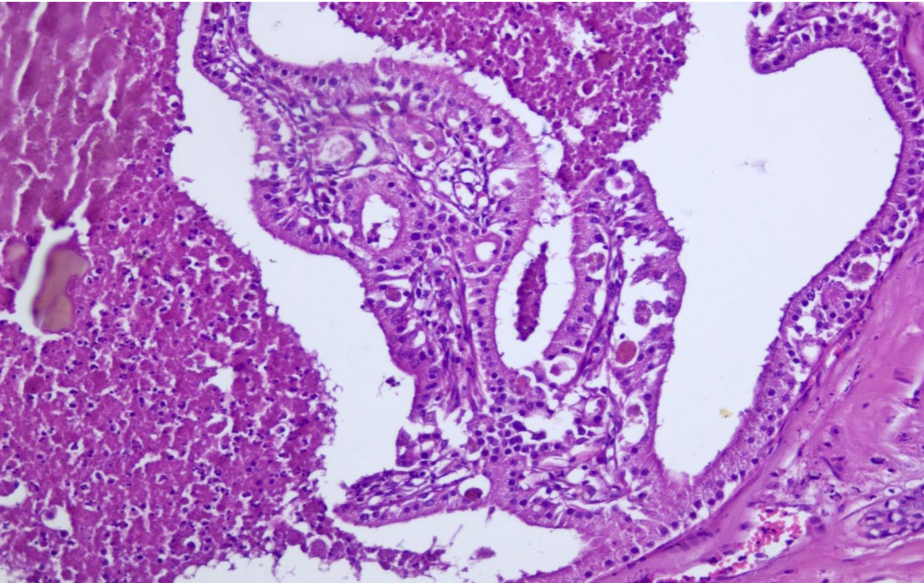

The deep dermis was expanded by an unencapsulated, well-circumscribed, multilobular neoplasm composed of two populations of cells (Fig. 1). The first population was composed of cuboidal to columnar cells forming varisized islands and well-differentiated tubules supported by a dense fibrovascular stroma. Neoplastic cells had indistinct cell borders, a small to moderate amount of granular eosinophilic cytoplasm (Fig. 2).

Within tubules, neoplastic cells frequently form few papillary projections into tubule lumina. Tubules contained necrotic debris and fragmented neutrophils. Ceruminous gland proliferation has areas of ectasia and hyperplasia as well as regional hyperplasia of sebaceous glands and pleocellular otitis externa.